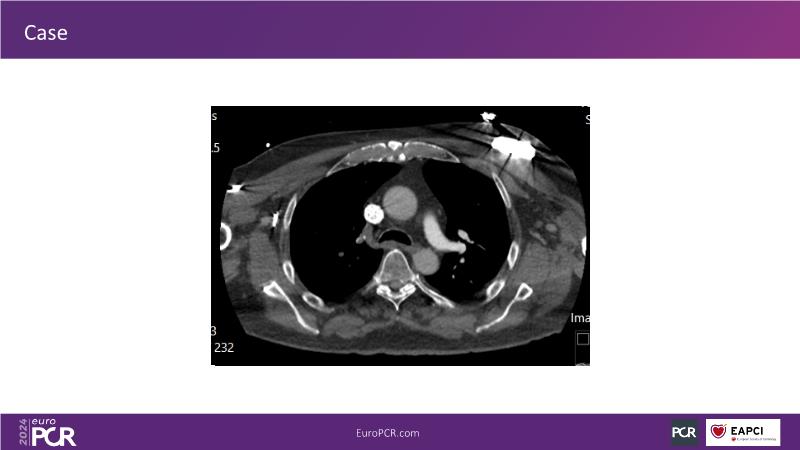

Advancing percutaneous treatment of pulmonary embolism with computer-assisted vacuum thrombectomy

Join this session to delve into innovations in computer-assisted vacuum thrombectomy for acute pulmonary embolism, leveraging real-life case scenarios to share practical experiences and discuss treatment strategies. Amidst the current surge in scientific research, ongoing trials like STORM PE and STRIKE PE are pivotal in shaping the landscape of pulmonary embolism management.